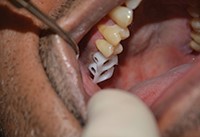

به دنبال پروتکل تجویز شده، یک پانچ بافت هدایت کننده 6.0 میلیمتری برای حذف بافت توپی متمرکز در اطراف سوراخ آزمایشی اولیه مورد استفاده قرار گرفت (شکل 4). اکنون که استخوان تاج در معرض قرار گرفته است، ابتدا استوئتومی بالایی 3.5 میلیمتری (شکل 5)، و سپس استوئتومی گسترده ی 5.7 میلی متری (شکل 6) استفاده شد. به طور معمول، با سیستم OCO، پروتکل اجازه ی پیشرفت از مرحله آزمایشی به قطر نهایی را در یک مرحله به دلیل طراحی منحصر به فرد مته می دهد.

شکل 4. یک پانچ بافتی هدایت کننده ی 6.0 میلیمتری.

شکل 5. استئوتومی 3.5 میلی متری پیشین.

شکل 6. استئوتومی 5.7 میلیمتری پیشین.

شکل 7. استئوتومی کامل.